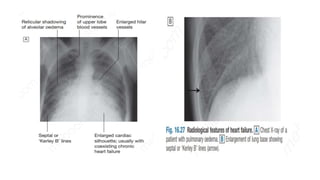

Chest X-ray

A chest X-ray should be performed in all cases

This may show -

• abnormal distension of the upper lobe pulmonary veins

• Vascularity of the lung fields becomes more prominent and

• The right and left pulmonary arteries dilate.

• Interstitial oedema causes thickened interlobular septa and dilated

lymphatics. These are evident as horizontal lines in the costophrenic

angles (septal or ‘Kerley B’ lines)

Chest X-ray A chestX-ray should be performed in all cases This may show - • abnormal distension of the upper lobe pulmonary veins • Vascularity of the lung fields becomes more prominent and • The right and left pulmonary arteries dilate. • Interstitial oedema causes thickened interlobular septa and dilated lymphatics. These are evident as horizontal lines in the costophrenic angles (septal or ‘Kerley B’ lines)